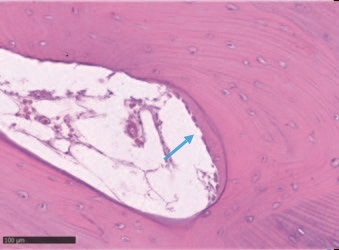

Гістологічний аналіз показав добре організовану, в основному зрілу тканину, утворену компактною пластинчастою кісткою, що характеризується чітко окресленими кістковими пластинками навколо каналів Гаверсіяна та Фолькмана, оточених меншими ділянками, в яких пластинки були менш організованими та багатими остеоцитами на стадії дозрівання . Кількість знайденої мінеральної матриці - від 69% до 72% - була особливо значною.

Рис. 10 – Як видно, в деяких медулярних просторах відбувається відкладення нового кісткового матриксу (синя стрілка). Кістка в пластинчастій формі свідчить про розвинений стан дозрівання тканини.

Рис. 11 – Блакитна область визначає ділянку з ймовірною присутністю носіїв, що припускає, що нова кістка могла бути відкладена саме з місця трансплантації.